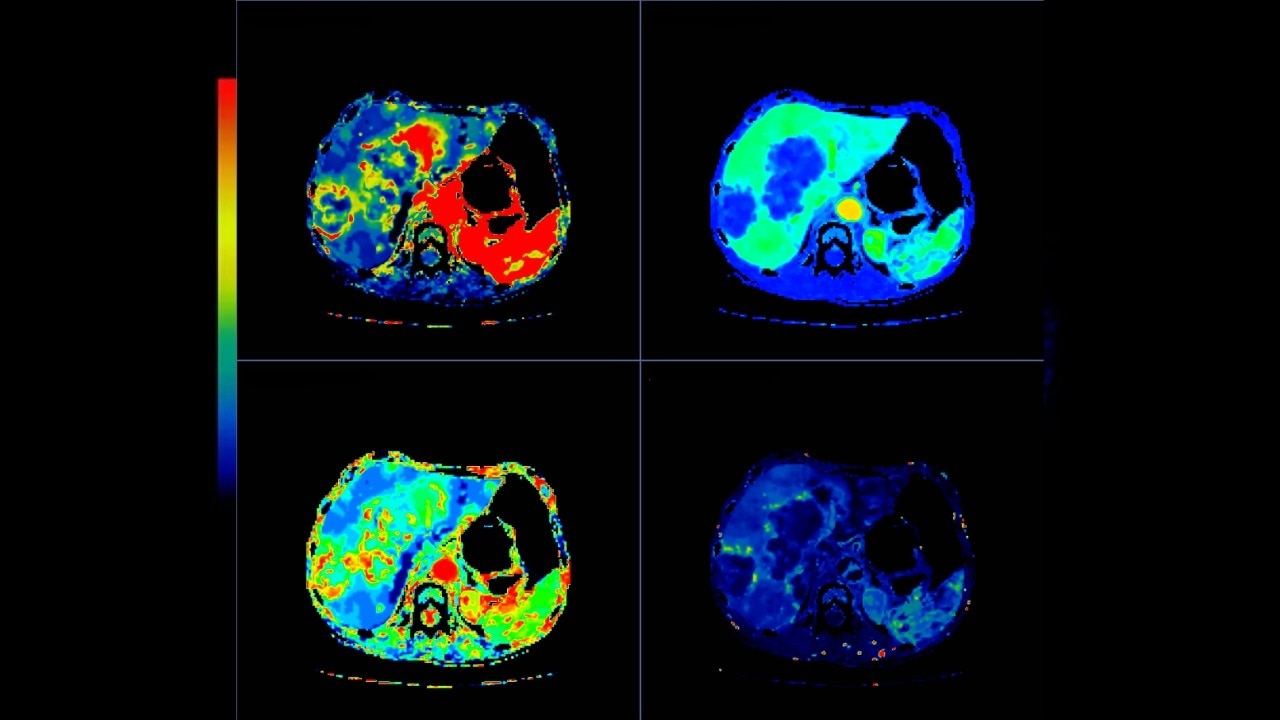

Optimized protocols for kidney, soft tissue, liver perfusion and other body tumors